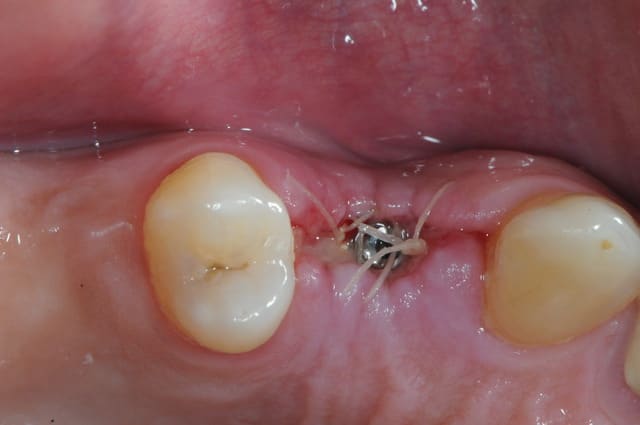

dis moi la tu le trouves comment mon compromis avec l'espace biologique

eii

d'après toi faites il y a combien de temps?

Superbe ratrapage suite à une operculisation d'une vis de couverture. Félicitations. Je te savais costaud béotien mais là tu m'impressionnes vraiment.

- pas de vis de couverture , pas d'operculisation!!

Même pas de lambeau pédiculé palatin!